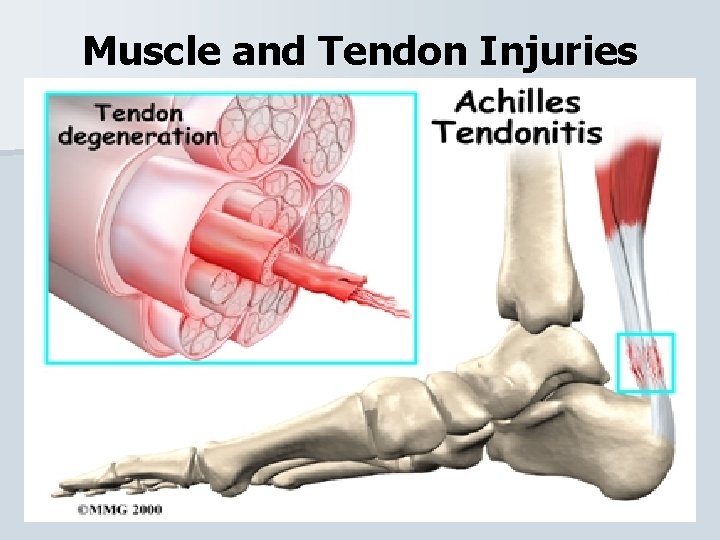

Muscle and Tendon Injuries

Muscle and Tendon Injuries Achilles Tendinitis Inflammation of the achilles tendon caused from repetitive stress (running and jumping) that cause the tendon to break down. • The athlete will have swelling tenderness, and crepitus and pain with dorsiflexion and palpation over tendon. • PRICE followed by stretching/strengthening. •